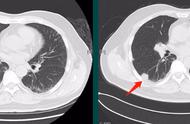

病例1:男性,53岁,间质性肺病每年定期体检,左图为4年前,右图为新近体检随访过程中发现右下肺胸膜下实性结节,穿刺证实为小细胞肺癌。